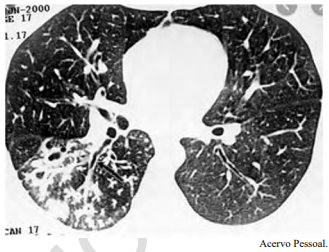

Um adolescente de 17 anos de idade procura atendimento em função de tosse vespertina, febre e hemoptise em pequena quantidade. Refere sudorese noturna e perda de peso. A tomografia de tórax apresenta nódulos centrolobulares com padrão de árvore em brotamento, além de pequenas cavitações espessas e de paredes irregulares, bem como brônquios espessados em segmento posterior do lobo inferior direito, conforme a imagem a seguir.

Tendo em vista esse caso clínico, a imagem apresentada e os conhecimentos médicos correlatos, julgue o item a seguir.

O paciente é forte candidato a tratamento com RHZE.